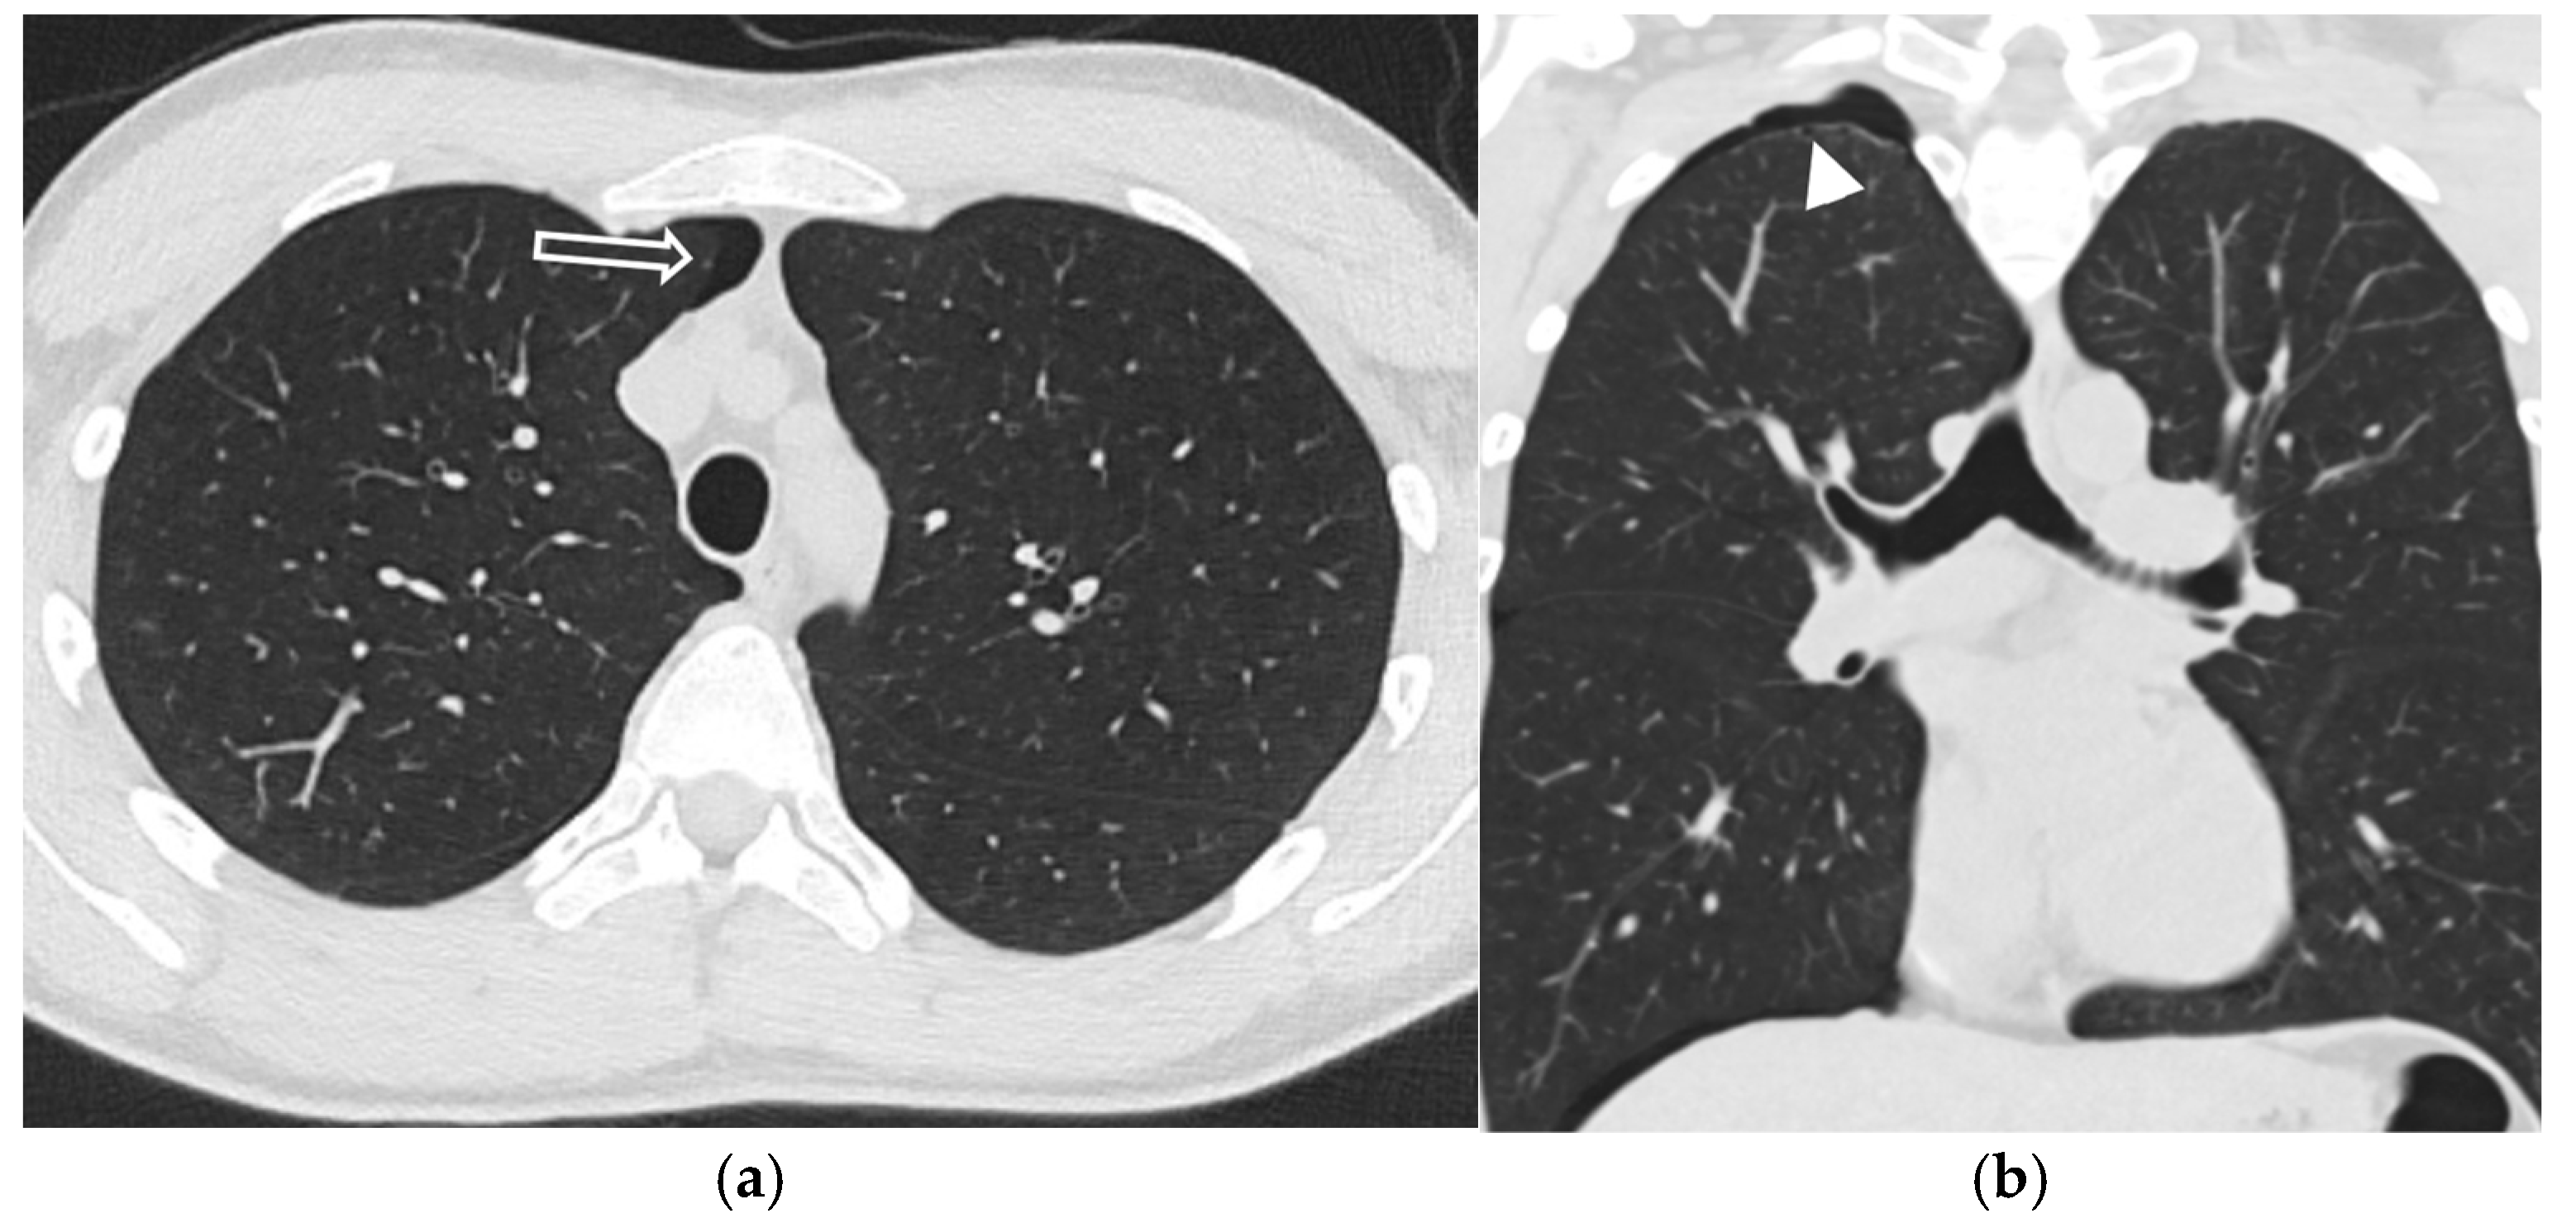

5.5.3. Birt–Hogg–Dubé Syndrome (BHDS)

5.6. Connective Tissue Diseases